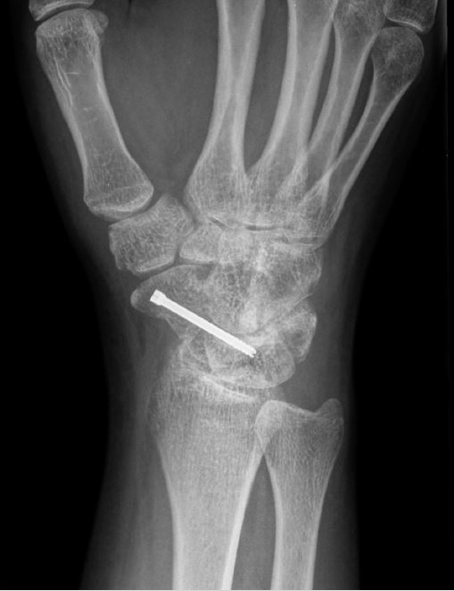

Medullary compression screws should be placed within the central 1/3rd of the scaphoid in both AP and lateral radio-graphs. This has been shown to have 43% stiffer construct and improved alignment and range of motion compared to eccentric placement. 8 Central placement has also been shown to have decreased time to union when compared with eccentric screw placement (► Fig. 41.3). 9